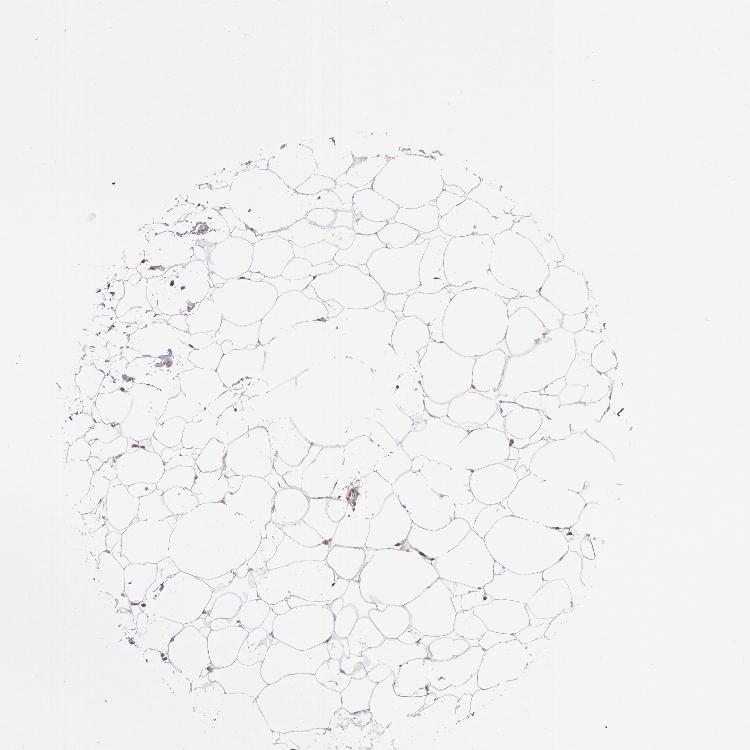

SOFT TISSUE 1 - Antibody stainingi

Antibody staining in the annotated cell types in the current human tissue is reported as not detected, low, medium, or high, based on conventional immunohistochemistry profiling in selected tissues. This score is based on the combination of the staining intensity and fraction of stained cells.

Each image is clickable and will lead to virtual microscopy that enables deeper exploration of all samples and also displays staining intensity scores, fraction scores and subcellular localization as well as patient and tissue information for each sample.

Antibody HPA001619Antibody HPA002078

Chondrocytes Not detected-

Fibroblasts Not detectedMedium